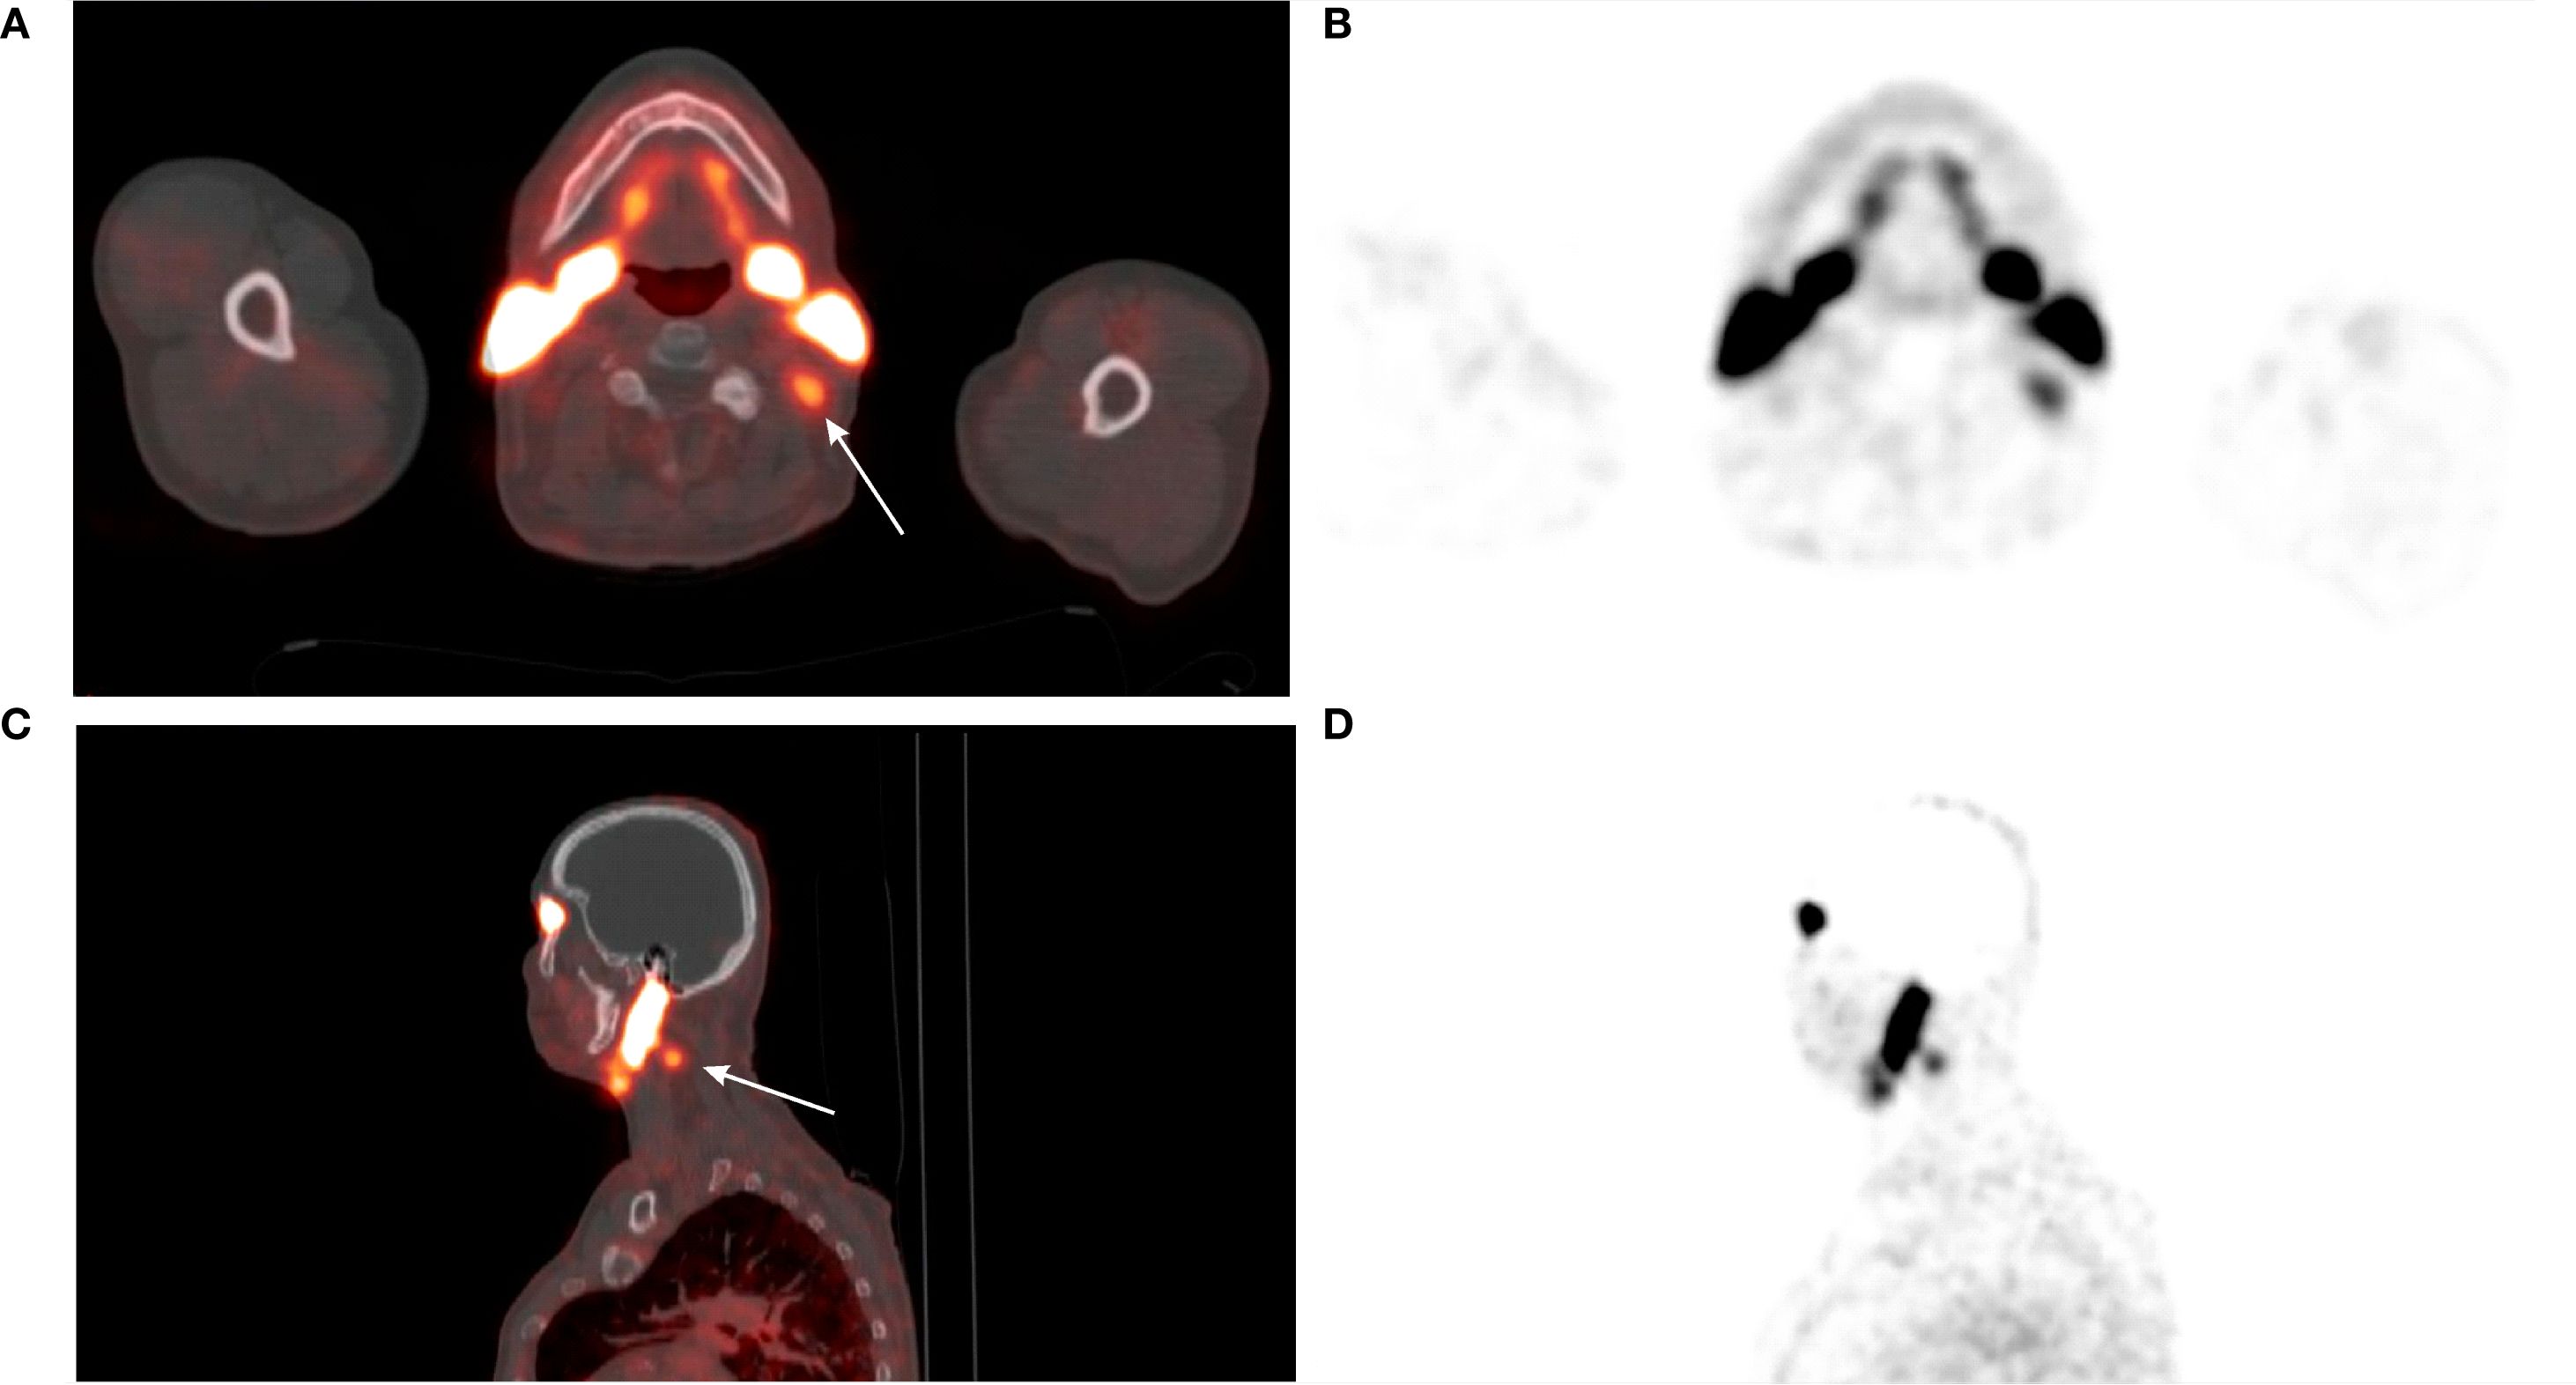

[68Ga]Ga-PSMA-11 PET/CT was positive in 5/12 patients – 3/3 patients with previously-identified structural lesions (a superior mediastinal mass, a metastatic cervical lymph node, and liver metastases; Figures 3–5) and 2/9 patients without previously known structural lesions. In both of these cases, [68Ga]Ga-PSMA-11 PET/CT revealed small lesions in the thyroidectomy bed, which could correspond to local recurrence or lymph nodes (one shown in Figure 6). The mean SUVmax, TBRBlood and TBRLiver values for detected lesions were 7.08 (range 2.74–12.37), 6.08 (range 3.19–9.82), and 2.23 (range 0.90–3.77), respectively.

Figure 3. (A) 64-year-old female with medullary thyroid carcinoma and a superior mediastinal mass. (A) [68Ga]Ga-PSMA-11 PET MIP. (B) [18F]FDG PET MIP. (C) Transaxial view of the fused [68Ga]Ga-PSMA-11 PET/CT scan (white arrow). (D) Transaxial view of the fused [18F]FDG PET/CT scan (white arrow). The superior mediastinal mass is more avid on [68Ga]Ga-PSMA-11 PET (SUVmax 7.98; TBRBlood 7.60) than on [18F]FDG PET (SUVmax 3.81; TBRBlood 1.85).